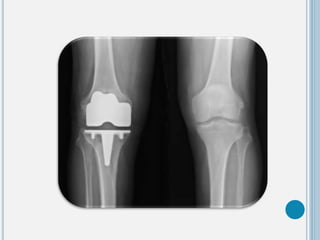

Clínico Rx

I. ↓ espacio articular

II. Esclerosis ósea subcondral

III. Formación de osteofitos

marginales

IV. Geodas (quistes

subcondrales)

V. Deformación con pérdida de

la alineación articular.

Estrechamiento del espacio

interarticular.

Hueso subcondral y escleroso

Disminución de los espacios femorotibiales

Cambios degenerativos con formación de osteofitos

Erosión de las superficies articulares y lesiones

http://osteomuscular.com/RODILLA/artropdegen.html